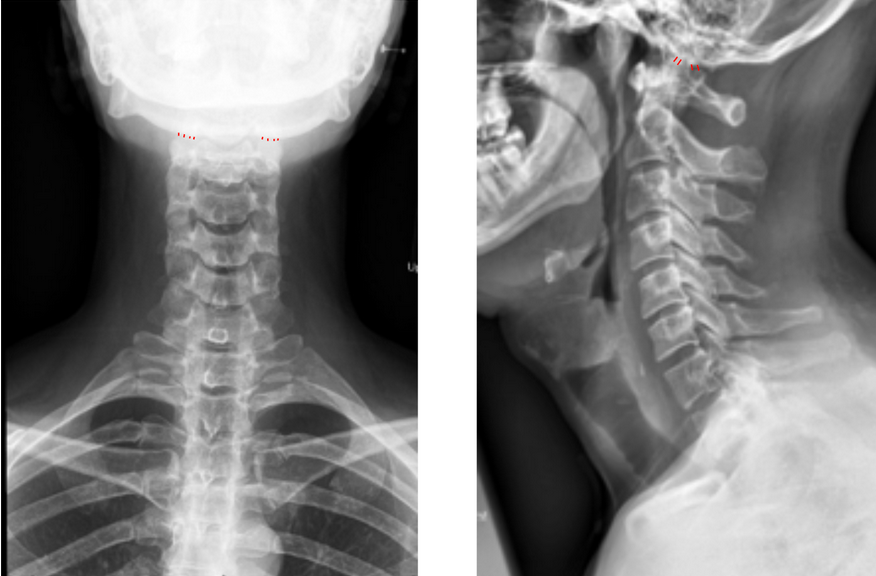

• Obtain both AP open-mouth odontoid and lateral cervical spine X-rays (as shown in the provided images).

• Identify landmarks on each side:

• Occipital condyle: The inferior articular surface of the occipital bone where it articulates with C1.

• Superior articular surface of C1 (atlas lateral mass): The concave superior facet just below the occipital condyle.

• On each side, measure the shortest perpendicular distance between the inferior margin of the occipital condyle and the superior margin of the C1 lateral mass.

• Record both the right and left CCI values and calculate the average.

• On lateral view, identify the posterior margins of the condyle and atlas and measure the shortest perpendicular distance between the inferior margin of the occipital condyle and the superior margin of the C1 lateral mass.